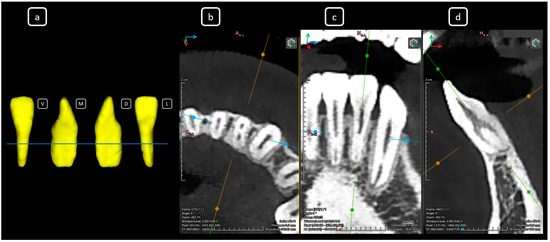

Cone beam computed tomography (CBCT) is a valuable diagnostic tool for evaluating the upper airway and maxillofacial region. This report demonstrates the clinical value of CBCT in identifying significant anatomical variations in endodontics, incidentally detected on a non-endodontic CBCT scan. A 23-year-old female patient underwent CBCT imaging at the Faculty of Dentistry-UJED to evaluate her upper airway. CBCT imaging revealed a unique, complex, and unusual anatomy of mandibular root canals, characterized by Vertucci’s type III root canals in the anterior sextant and co-occurrence of bilateral C-shaped mandibular second molars (type C2 according to Fan’s classification). No therapeutic interventions were initiated due to the patient’s asymptomatic status. CBCT imaging is a valuable tool for integrated diagnostic approaches, underscoring its role in thorough patient management. The integration of multidisciplinary interpretation of CBCT data can enhance diagnostic accuracy and optimize patient records and management, emphasizing the importance of collaborative efforts between radiologists, clinicians, and endodontists. Documenting and sharing such findings can increase awareness of rare anatomical variations, facilitating detection and contributing to medical knowledge. Full article

Figure 1